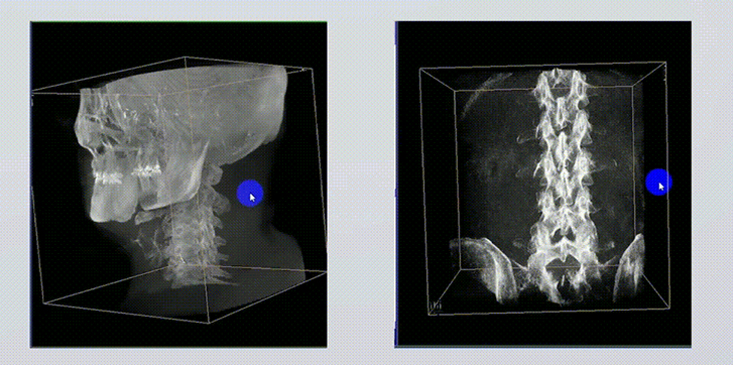

1、術(shù)中實(shí)時(shí)三維成像

術(shù)中三維成像和橫斷面圖像提供多角度的手術(shù)診斷信息,輔助醫(yī)生進(jìn)行術(shù)中評(píng)估判斷,諸如骨折復(fù)位情況和內(nèi)植入螺釘?shù)某叽绾臀恢茫o助手術(shù)更好地完成。

提供更大的術(shù)中三維成像視野,采集更多圖像信息,可一次拍全全段頸椎、全段腰椎、七節(jié)胸椎、雙側(cè)骶髂關(guān)節(jié)、股骨頭及單側(cè)盆骨。